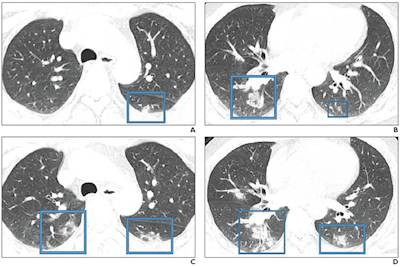

"An investigation of initial chest CT findings in 21 individuals with confirmed COVID-19 reported abnormal findings in 86% of patients, with a majority having bilateral lung involvement," the authors wrote.

"Although the imaging features [of COVID-19] closely resemble those of MERS and SARS, involvement of both lungs on initial imaging is more likely to be seen with COVID-19," the group wrote. "Initial chest imaging abnormalities in SARS and MERS are more frequently unilateral."